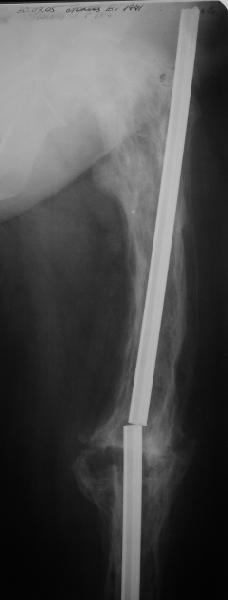

Еще один пример. Пациентка с юга России, прислала рентгенограммы через год. На сегодня прошло 2 г. 8 мес. после операции. Несмотря на не очень убедительный процесс сращения, пациентка ходит. Учитывая остеопороз при Педжете, решили, что динамизировать вообще не нужно.